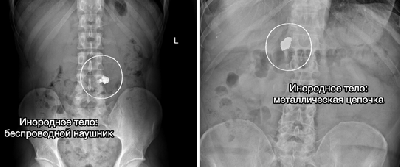

Всё это «достали из пациентов» врачи Склифа в 2025 году

еред вами - подборка самых неожиданных «находок» ушедшего года⠀

Специалисты удаляли беспроводные наушники, украшения и даже гвозди, зажатые в зубах и ненамеренно проглоченные в процессе ремонта.

Случаи курьезные, но проблема крайне серьезная - ежегодно в НИИ поступают десятки пациентов с инородными телами. Им требуется экстренная медицинская помощь и зачастую длительное восстановление.